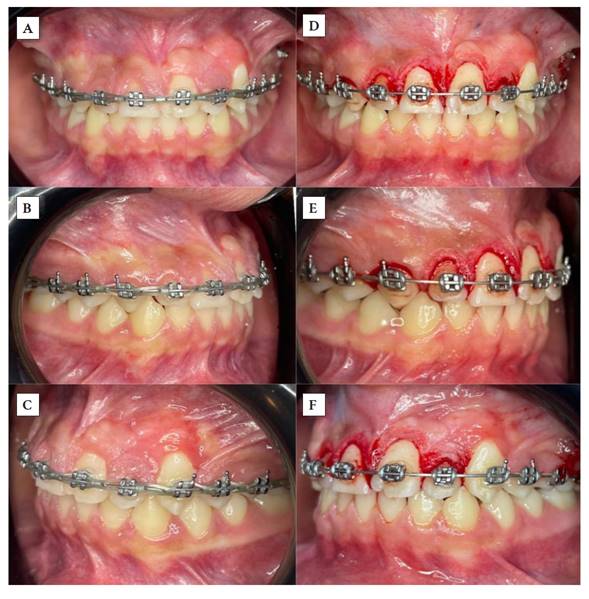

Inicialmente, se realizó la exodoncia del canino primario superior izquierdo para mejorar el corredor de erupción del incisivo central superior permanente. En la fase de ortodoncia inicial se coloca la aparatología fija con prescripción de Roth slot 0,22, exclusivamente en las UD 24, 25 y 26, además de un minitornillo como anclaje absoluto en la zona molar izquierda para tracción distal del canino superior (UD 23) y evitar así mesializaciones no deseadas al consolidar dicho sector. Al ubicar la UD 23 en su posición correcta, la UD 21 erupcionó posterior a destrabar ese espacio. Después de observar que dicha unidad dentaria iba erupcionando, se realizó un ojal quirúrgico y se cementó un bracket en la UD 21 y en el resto de la arcada superior para continuar con los pasos de alineación y nivelación, siguiendo la secuencia de arcos con normalidad en la ortodoncia correctiva (Figuras 4 y 5).

Al tener los dientes en su correcta disposición, se apreció que el paciente presentaba una topografía gingival asimétrica, por lo que se procedió a realizar gingivectomía y gingivoplastia del sector anterosuperior para obtener un contorno más estético y fisiológico del tejido blando (Figura 6). Siguiendo un orden, se observa un exceso de encía queratinizada en algunas unidades dentarias; por ejemplo, en la UD 23 se identifica una banda muy estrecha. Además, es necesario realizar ajustes en la estética dental para armonizar la anatomía dentaria, lo cual también repercute en la evaluación de los parámetros estéticos.

En un estudio realizado en pacientes con dientes traumatizados, se detectaron anomalías dentales en los dientes permanentes sucesores en 21 pacientes, en 26 dientes y 28 anomalías. Lo más frecuentemente encontrado fueron anomalías del proceso eruptivo, después la hipoplasia del esmalte y las manchas blancas. Si el traumatismo era en menores de 36 meses, se encontró que el porcentaje de anomalías era más frecuente. Las luxaciones intrusivas y extrusivas se vincularon con alteraciones clínicas en los dientes permanentes sucesores. Se señala en esta investigación el riesgo de anomalías dentarias posterior a un trauma en dentición primaria 15. En el presente caso reportado, al analizar la radiografía panorámica, se observó una imagen en la zona del tercio incisal del incisivo central superior izquierdo permanente, que al erupcionar se pudo evidenciar que era una hipoplasia dental. Asimismo, al realizar radiografías posteriores, se apreció una dilaceración radicular en el incisivo lateral del mismo lado (Figura 7). De Amorim et al. 16 encontraron, entre un grupo de 815 dientes primarios traumatizados, que las secuelas más comunes observadas en los dientes sucesores fueron decoloración del esmalte, hipoplasia dental, y dilaceración radicular y de la corona. Todos estos datos coinciden con las manifestaciones bucales encontradas en el presente reporte de caso.

Los conceptos de gingivectomía y gingivoplastia generalmente van de la mano, y se indican en casos de surcos supraóseos, surcos mayores de 3 mm, cuando no hay necesidad de cirugía ósea, topografía asimétrica y antiestética de la encía, alargamientos gingivales. Debido a estas razones, al paciente se le realizaron dichas intervenciones.